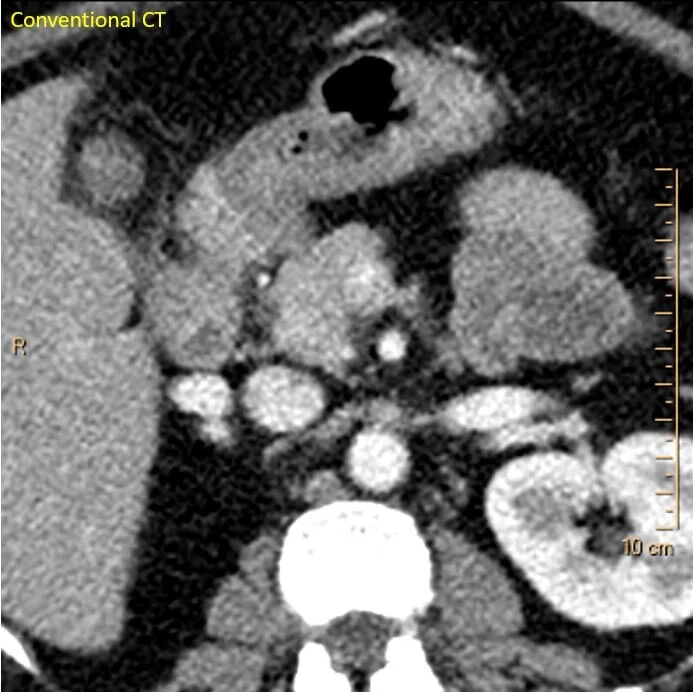

A 50 yo female presents to the ED for abdominal pain. She has a history of multiple prior bowel surgeries, and a CT scan is requested. I do not see an acute finding on the CT, and as I am going through my search pattern, the pancreas looks normal.

Conventional CT: Not much to talk about